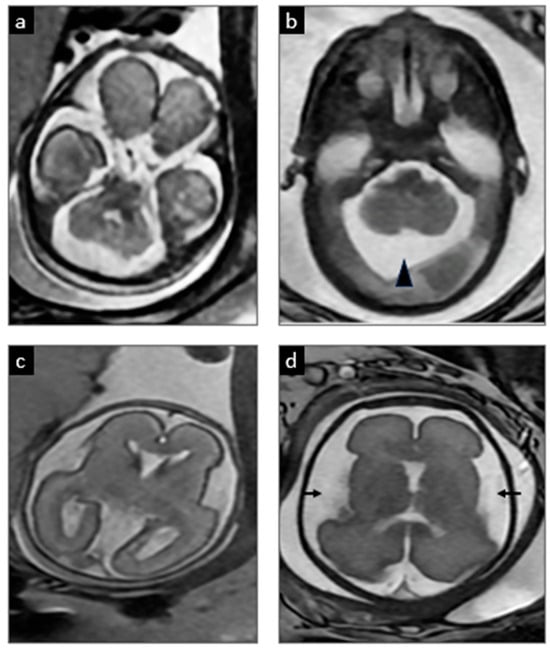

| 10 | Lubout et al., 2018 (Patient A) [10] | Yes (via chorionic villus sampling) | Fetal MRI normal until ~36 wk; then mild ventriculomegaly and subtle white-matter T2 hyperintensities observed | Day 0 (~4 h after birth) | 36 + 4 w | Neonatal seizures controlled; at 41 mo ~30–35 mo developmental level (Bayley ~16th percentile) with persistent macrocephaly (HC > P98; familial trait) |

| 11 | Lubout et al., 2018 (Patient B) [10] | Yes (via amniocentesis at 32 weeks) | Fetal MRI from 32 wk: mega cisterna magna with slightly small cerebellum; by 36 wk mild ventriculomegaly and subtle white-matter T2 hyperintensities | Day 0 (~5 h after birth) | ~39–40 wk | Only brief subclinical neonatal seizures (on aEEG) at 41 mo~18–26 mo developmental level (Bayley; cognitive ~5th, motor ~0.5th percentile), with clumsy gait |

| 16 | Etchegaray et al., 2025 (this case) | Yes (16 w via amniocentesis) | Fetal MRI normal at 22 w; mega cisterna magna at 28 w | Day 0 (within 10 min of birth) | 32 w 6 d | Neonatal seizures (resolved by 60 h); discharged D37. Developed dystonic quadriplegic CP by 6 mo (cognition relatively spared); remains seizure-free at 24 mo |